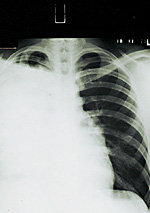

Ежегодно в России 56 тысяч человек погибают от рака легкого. Сегодня появился шанс переломить ситуацию в лучшую сторону — российским врачам стал доступен молекулярный метод лечения, позволяющий стабилизировать опухоль не только на ранних, но и на самых поздних стадиях. Об этом шла речь на прошедшем в Москве Всероссийском симпозиуме онкологов и хирургов.

— Молекулярно направленная терапия — это принципиально новый подход к лечению онкологических больных, - говорит профессор Вера Горбунова из Российского онкологического научного центра им. Н Н. Блохина. — Основан он на применении таргетных препаратов, блокирующих способность онкологических клеток к росту. В отличие от традиционных противоопухолевых средств, эти препараты не вызывают характерных для химиотерапии побочных эффектов. Словом, даже когда опухоль находится в запущенном состоянии, данный механизм блокировки приостанавливает всякое дальнейшее развитие опухоли, после чего мы ее сможем совершенно безопасно удалить или оставить — если она не мешает человеку жить.

Правда, о широком применении препарата пока нужно говорить осторожно — еще не завершены все испытания.